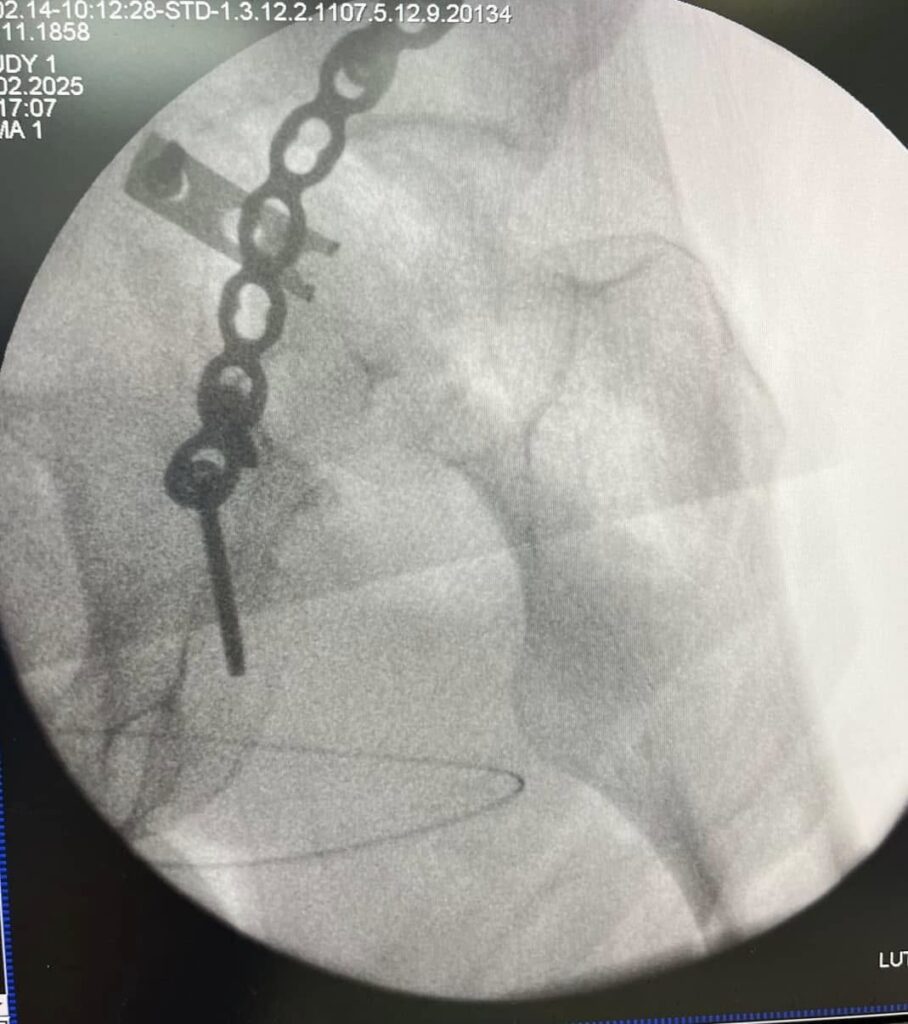

Возможно, что вы помните примерно двухнедельной давности наш с друзьями пост «Ампутировать или сохранять?». Речь шла о буквально разрушенном плече у воина ЗСУ в результате минно-взрывного ранения.

На первых этапах несколько великолепных и эффективных операций коллеги из института им О.О. Шалимова выполнили. В том числе и пластику торакодорзальным лоскутом. На видео как раз рука после этих этапов реконструкции.

А дальше пришел наш черед. Сразу выполнять и фиксацию, и пересадку кости мы не стали. Почему? Клебсиелла раньше в ране жила. А это страшная бактерия, что все труды разрушает. Как кариес зуб – вот так же точно «сгрызает» кость. Особенно «любит» только что пересаженную.

Поэтому сначала выполнили только фиксацию из малых доступов. И взяли ткани «на посев». Сеяли и на аэробные, и на анаэробные бактерии.

Никакого роста. Всё стерильно.

Поэтому следующим этапом мы (доктора Долгош Д.В., Никитин П.В., Парий В.Б. и ваш покорный слуга) взяли 12 см малоберцовой кости (свободный трансплантат) и кортикальную кость из бедра пациента с помощью RIA-2. Как раз этот этап на фото. Черно-белом, чтобы Фейсбук меньше возмущался. Там в фильтре-боксе как раз костная крошка из бедра видна. А она, как вы понимаете, красного цвета . Всё это перемешали еще и с BONALIVE (заменителем кости нового поколения с антибактериальным эффектом) и имплантировали. С ещё одной дополнительной пластиной.

Так что вот такой у нас праздник праздничный.

Поэтому вместе с фиксацией этой реально разрушенной плечевой кости (см рентгенограмму) пластиной из минидоступов, мы с Vasyl Parii и Денисом Долгушем не стали одномоментно делать и массивную костную пластику. Взяли ткани снова на посев. Если посев будет стерилен, то следующим этапом сделаем пластику. Если нет, – то вновь проведем антибактериальную мощную терапию.

Затем предстоит вмешательство на плечевом сплетении (есть повреждение). Когда (если) всё пройдет успешно, то вместе с пациентом решим, что делать с плечевым суставом. Скорее всего его замыкание (почти нет дельтовидной мышцы и элементов вращательной манжеты; не знаем объёма восстановления сплетения (положительная динамика есть)).